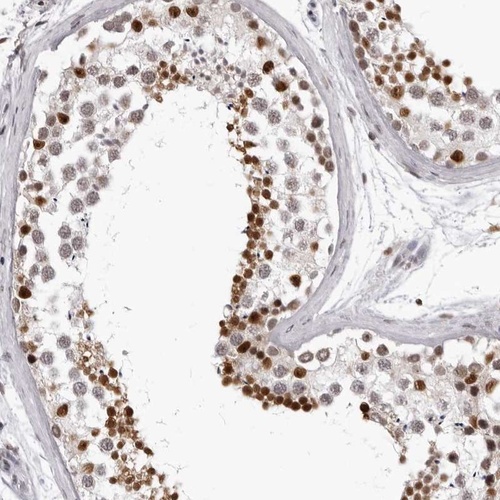

Immunohistochemistry analysis in human testis and heart muscle tissues using Anti-HEXIM2 antibody. Corresponding HEXIM2 RNA-seq data are presented for the same tissues.